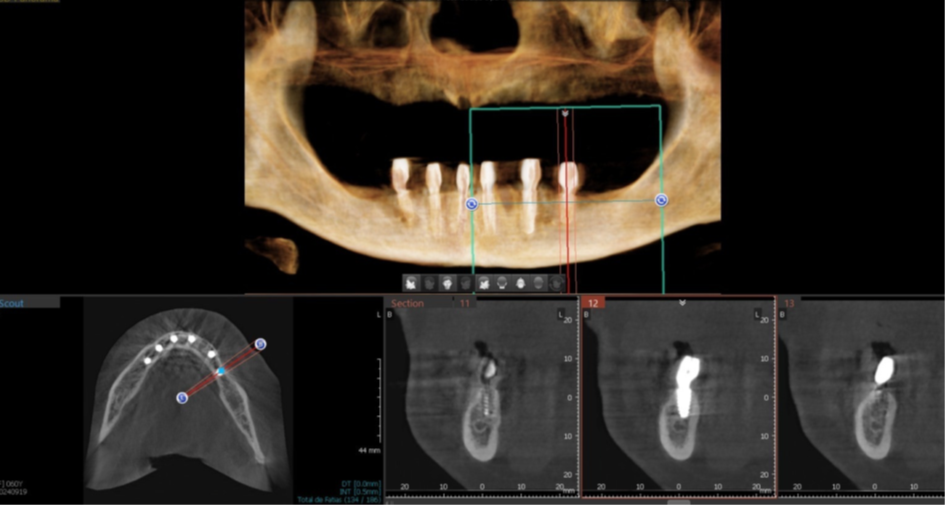

Foram planejados seis implantes nas seguintes medidas: elemento 31: 3.5x11mm; elemento 33: 3.5x11mm; elemento 35: 3.5x7mm; elemento 41: 3.5x11m; elemento 43: 3.5x11mm; elemento 45: 3.5x7mm; que foram distribuídos ao longo da mandíbula. O planejamento virtual do guia cirúrgico foi realizado em parceria com a empresa TechnoGuide, sendo posteriormente validado e aprovado para a confecção do guia definitivo.

Figura 8 – Planejamento digital do implante 31.

Figura 9 – Planejamento digital do implante 33.

Figura 10 – Planejamento digital do implante 35.

Figura 18 – Corte tomográfico implante 45.

Figura 19 – Corte tomográfico implante 43.

Figura 20 – Corte tomográfico implante 41.

Figura 21 – Corte tomográfico implante 31.

Figura 22 – Corte tomográfico implante 33.

Figura 23 – Corte tomográfico implante 35.